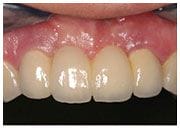

治療後